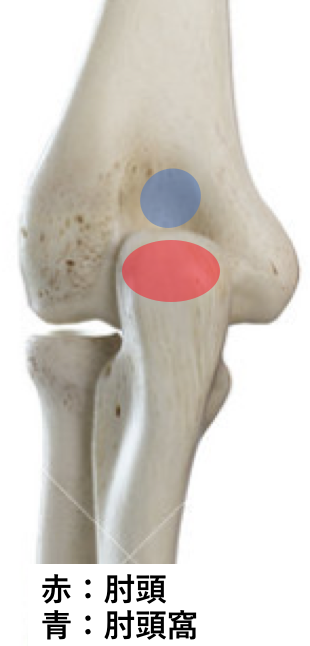

肘頭疲労骨折(投球障害肘(後方))

投球時の減速期に上腕三頭筋の力により肘頭が肘頭窩に接するが、その際に肘が外側に捻られ肘頭内側が肘頭窩に繰り返し衝突する事で疲労骨折が生じると言われています。